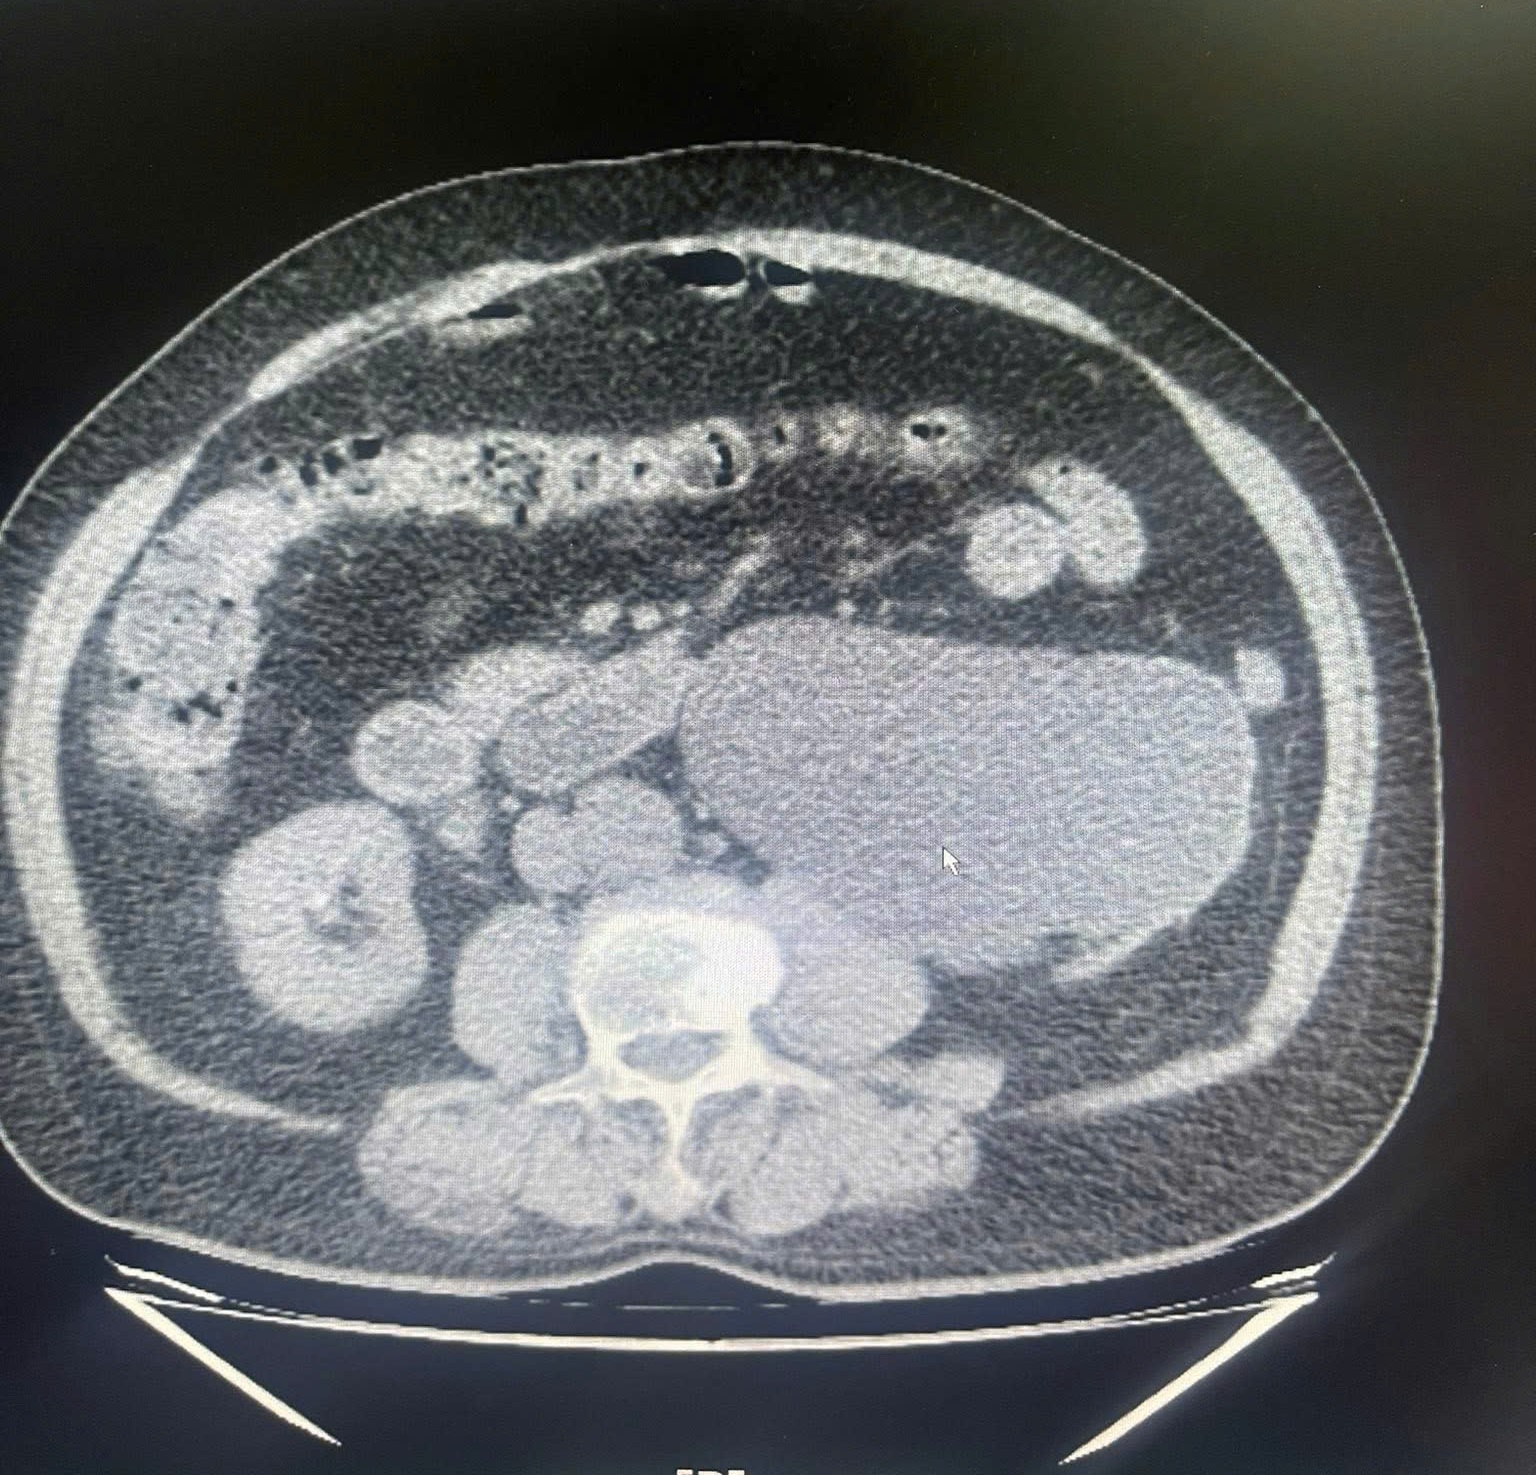

Người bệnh bị thận mất hoàn toàn chức năng do sỏi niệu quản. Ảnh: BVCC.

"Sỏi đường tiết niệu nếu không được phát hiện và điều trị kịp thời có thể gây tắc nghẽn kéo dài, dẫn đến ứ nước thận, nhiễm trùng tiết niệu tái diễn. Khi tình trạng này kéo dài, chức năng thận sẽ suy giảm không hồi phục, buộc phải cắt bỏ thận để bảo toàn tính mạng người bệnh", bác sĩ Nguyễn Hồng Long cho biết.